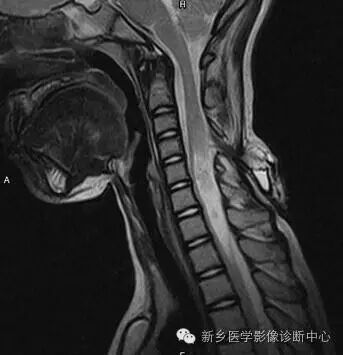

脊柱MRI提示椎管内占位及相应水平椎体后缘扇贝样压迹(白箭)

单发的扇贝样压迹最常见的原因为椎管内肿瘤引起椎管内压力增高,局部 向前压迫椎体后缘所致,如室管膜瘤、神经鞘瘤。

多发扇贝样压迹的原因包括椎管内多发占位(神经纤维瘤病)、交通性脑积水引起的椎管内压力增高、脊膜膨出以及软骨发育不全。